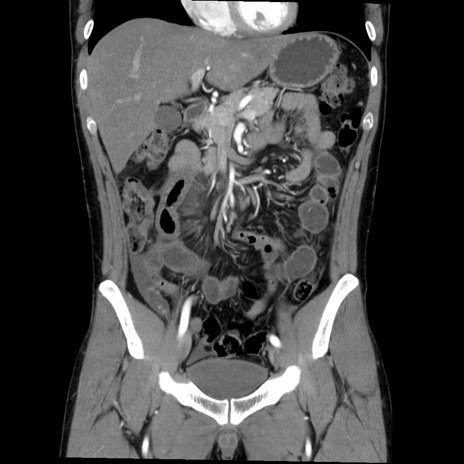

症例36(冠状断像)

【症例】20歳代 男性

【主訴】心窩部痛

【現病歴】今朝より上腹部痛あり。一旦軽快していたが再度出現したため救急要請。昨日夕に白身の魚を含む刺身を食べた。

【身体所見】BP 136/89mmHg、HR 74/min、BT 37.0℃、腹部:膨満、軟、心窩部に圧痛あり。反跳痛なし、筋性防御なし、腸雑音やや亢進あり。

【データ】WBC 17700、CRP 0.48